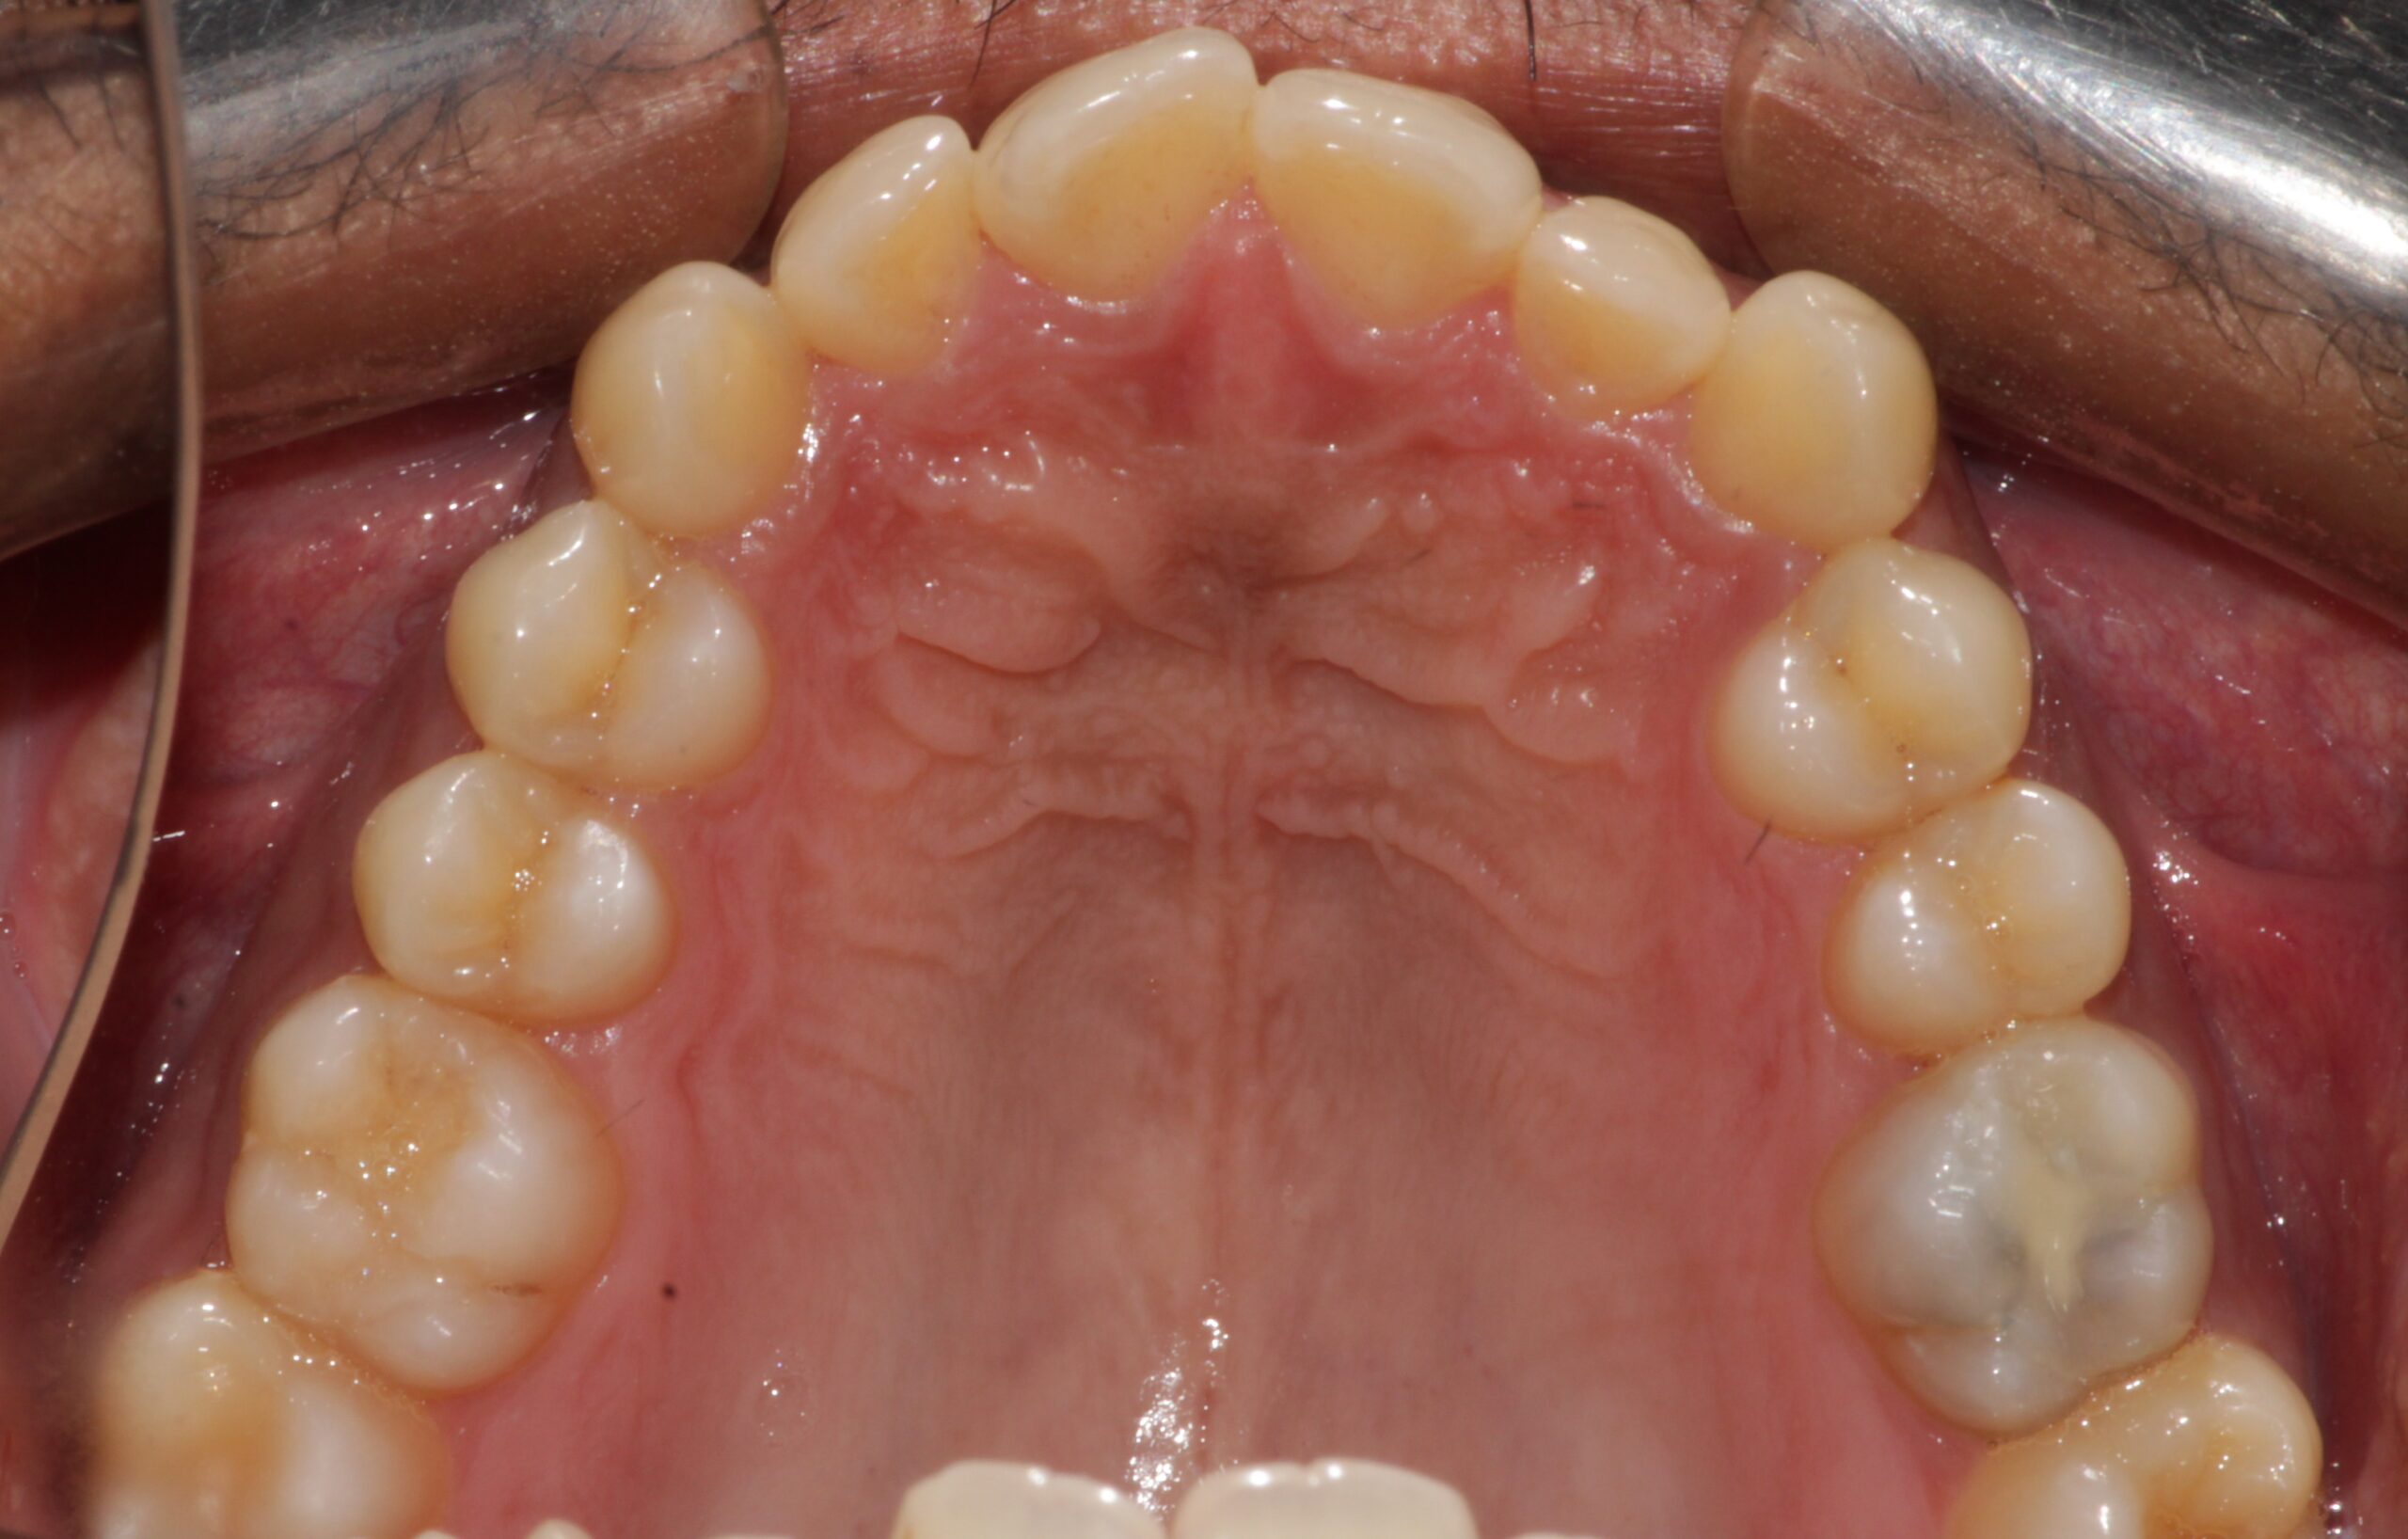

Before: Upper

The patient had teeth crowding and a crossbite, where a lower tooth was biting in front of an upper tooth. This condition led to the accumulation of plaque, tartar, and cavities.

If left untreated, it could have caused possible loss of teeth in the long term due to gum disease or cavities, as crowded teeth are difficult to clean effectively with regular brushing.

The patient underwent aligner therapy using Invisalign aligners to correct the crowding and crossbite, ultimately giving the patient an improved smile.